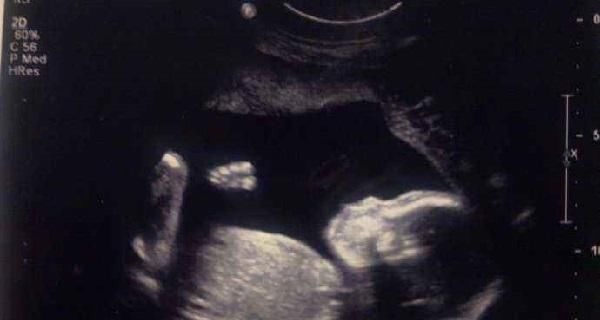

但是蓉蓉的婆婆却不是很高兴,因为是鼠年,婆婆出于“十鼠九苦” 的迷信说法,希望他们放弃在今年怀孕的计划,明年再生一个属牛的宝宝才会更圆满。而且再加上近段时间蓉蓉单位恰好有一个外出培训的机会,她非常希望参加,但是没想到在这个时候怀孕了,因此她也想缓一缓再生孩子。于是在老公的陪同下到医院做流产手术。手术前检查的时候,一个慈祥的老医生听了他们的要求后严肃的批评道:“你们太无知了,头胎宝宝是上帝的礼物,是来报恩的,这样胡闹于心何忍?”

蓉蓉当时很不明白,这个老医生怎么还如此迷信呢?老医生见他们一脸懵懂,细细的说出了4个反对的理由,蓉蓉夫妻听完后深为自己的无知而自责。那么,医生为什么不主张不要头胎宝宝呢?这个时候的胎儿发育情况最好,排除身体健康的原因,选择放弃宝宝非常令人可惜。